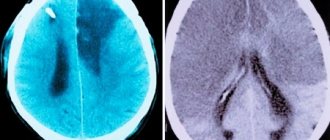

• Computed tomography - if time and resources allow. It is the most reliable diagnostic method.

Click on the image to enlarge